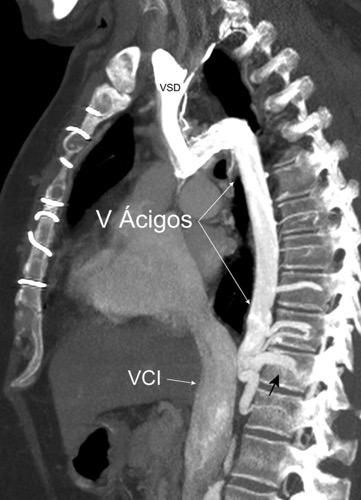

1. Obstrucción por encima de la V Ácigos. (La sangre llega al corazón a través de ella)

2. Obstrucción con participación de la V. Ácigos. (La sangre utiliza otras alternativas para llegar al corazón vía VCI).

Participación de la V. Ácigos como vía principal para llegar a la VCI.

Contiene: Grasa. Aorta y ramas

Venas ácigos y hemiácigos

Troncos simpáticos y nervios esplácnicos